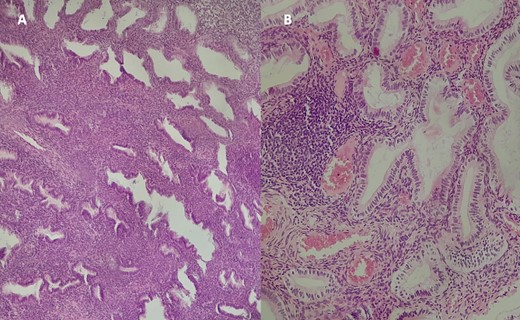

An ultrasonic polypectomy was performed with the Harmonic scalpel under general anaesthesia. The polypectomy specimen (Fig. 4) was sent to the pathology laboratory, where histopathological examination revealed endometrial glands without signs of dysplasia or malignancy (Fig. 5). The patient underwent a postoperative follow-up without experiencing any further vaginal bleeding. The final diagnosis was a voluminous cervical polyp delivered through the uterine cervix, measuring 5 cm, with no signs of malignancy.

Histological examination of the excised specimen with Hematoxylin–Eosin staining at ×10 magnification (A) and ×40 (B) revealing endometrial glands of variable size and shape, often dilated and cystic, lined by a regular pseudostratified cylindrical epithelium. The stroma is cytogenetic with hemorrhagic changes, without signs of dysplasia or malignancy.